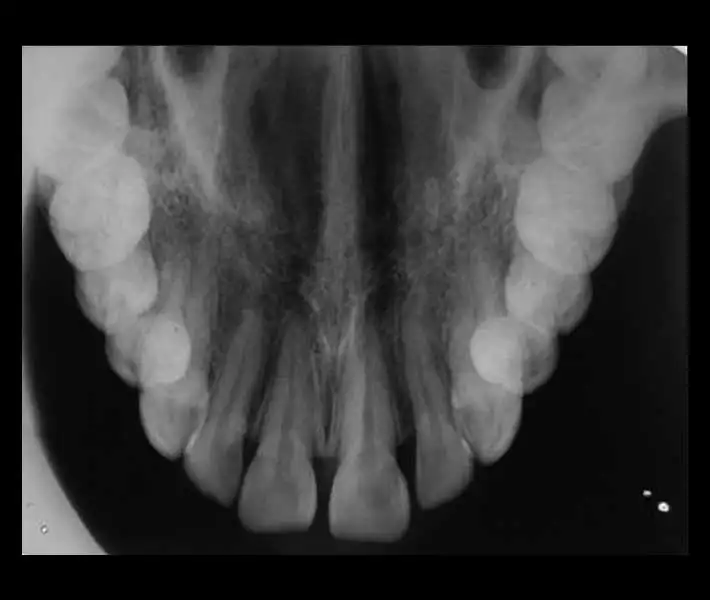

- رادیوگرافیهای داخل دهانی (پری اپیکال ،اکلوزال ،بایت وینگ)